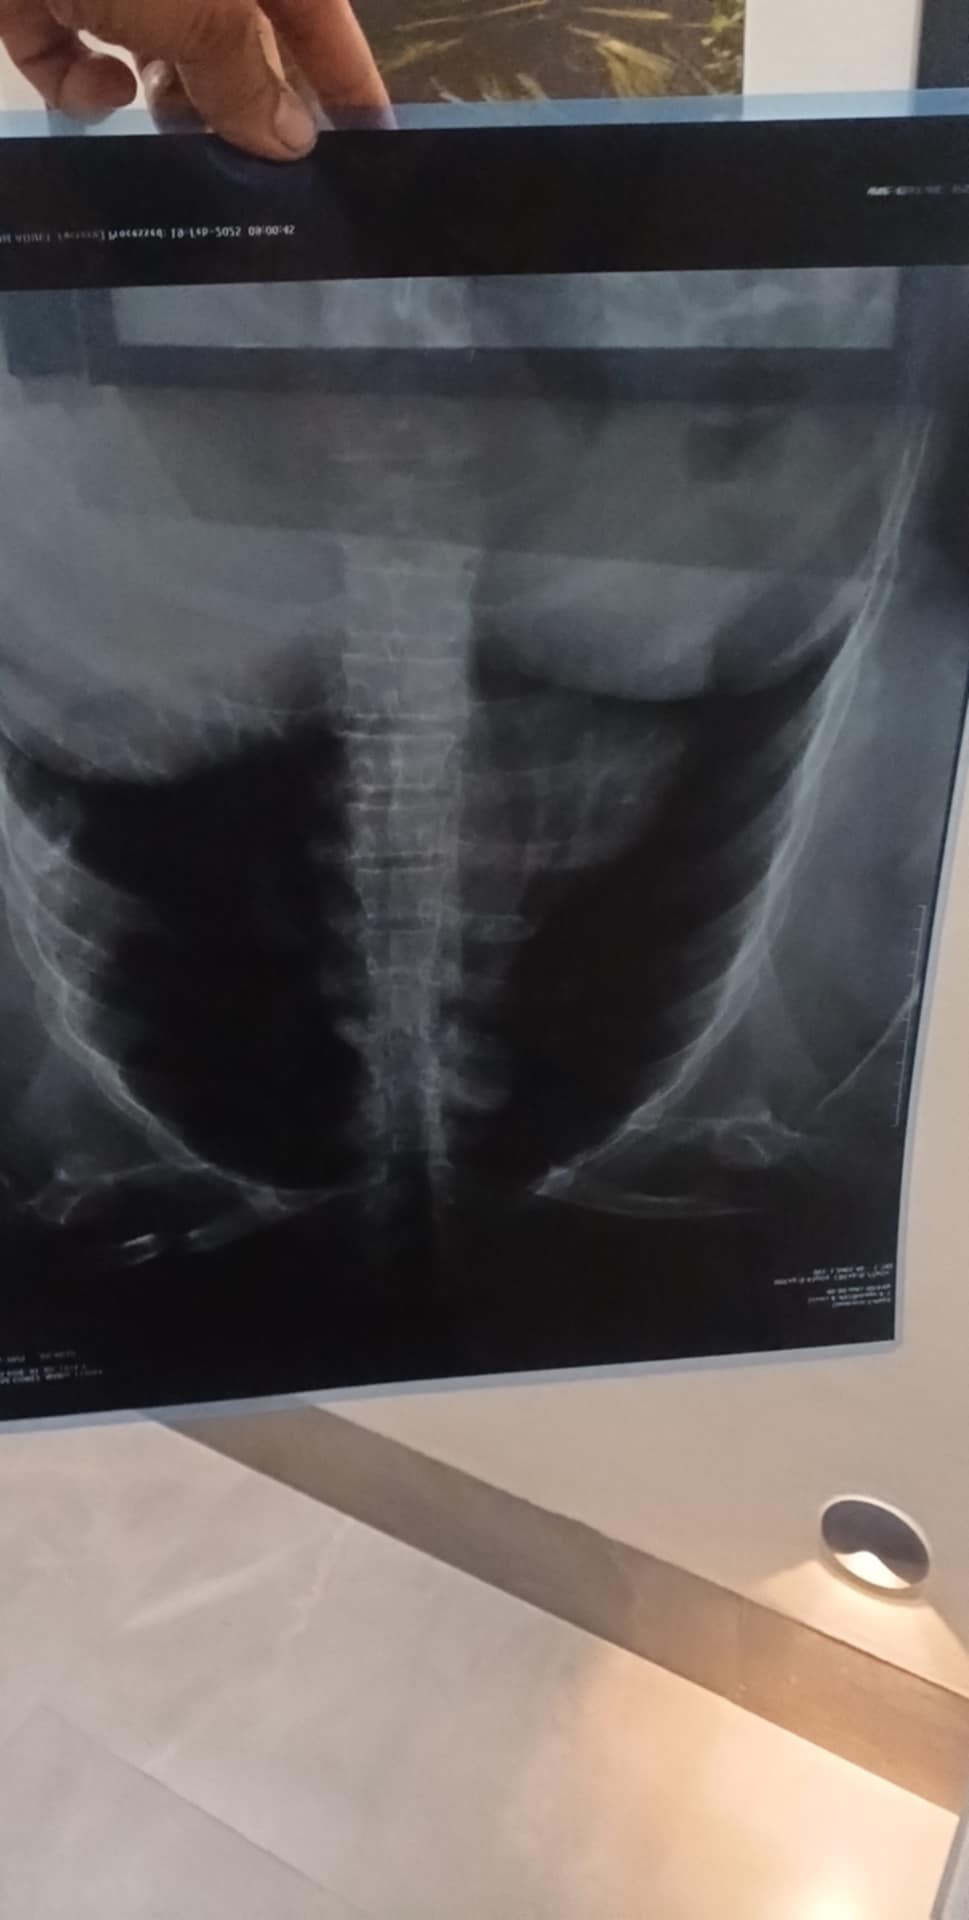

Se requiere una operación urgente para la señora Ma. Esther aguilar gomez que fue atropellada el pasado miércoles 19 de febrero del año 2025 la operación consiste en una cirugía de espalda de la lumbar 1 y lumbar 2 que llevará acabó el doctor Bulmaro Morales el día lunes 24 de febrero del presente año agradeciendoles de antemano a todas las personas de buen corazón por su apoyó y bendiciones gracias